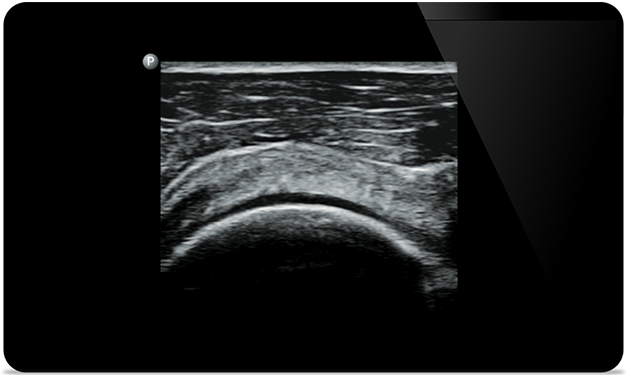

Lumify helps you see the fine details in muscles, joints, ligaments, tendons and cartilage to make a more accurate diagnosis of injuries.

Lumify can help you assess patients from head to toe, whether it’s plantar fasciitis, tendonitis or bursitis in the patellar tendon, or even shoulder instability in the rotator cuff.

knee arthrocentesis